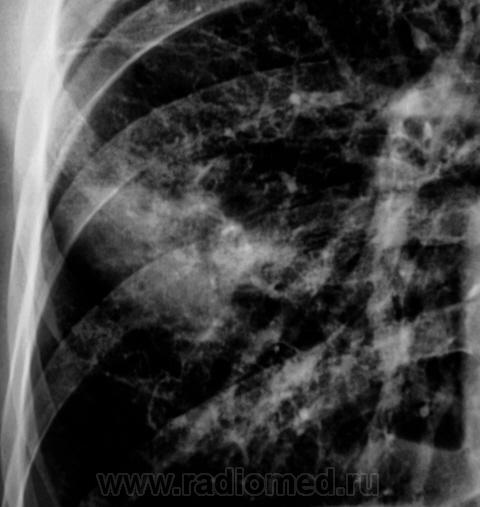

Еще контроль через 1 месяц.

Распад был изначально, но, к счастью больного, все закончилось практическим выздоровлением.

Долго что-то пневмонию лечили. А распад очень сомнительный. Больше на игру теней похож.